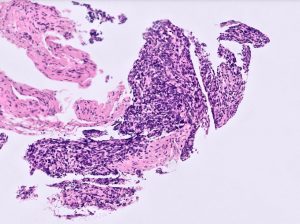

A female patient in her 40s presented with renal impairment. CT intravenous pyelography demonstrated longstanding right hydronephrosis and hydroureter with lower ureteric obstruction. At ureteroscopy there was a lesion in the right lower ureter that was biopsied (three biopsies, each 1mm). This was followed by right distal ureterectomy and ureteric reimplantation. The first four images are from the diagnostic biopsy and the last image is from the resection specimen.

The biopsies showed small glands lined by simple columnar epithelium with cells showing basal elongated nuclei and scant apical eosinophilic cytoplasm. The surrounding stroma was cellular and composed of bland spindle cells with hyperchromatic nuclei with focal crush artefact. Keratin AE1/AE3 and PAX8 were expressed in the glandular cells only. The stromal cells were diffusely positive for CD10. ER was expressed in both glands and stroma. Neuroendocrine (NE) markers (synaptophysin, chromogranin A and INSM1), CD45, CD20, SS18-SSX and SSX-CT were negative. A diagnosis of ureteric endometriosis was rendered.